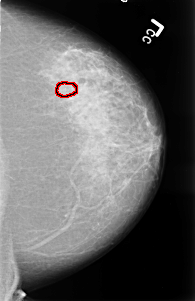

B_3476_1.LEFT_MLO

B_3476_1.LEFT_CC

FILE: B_3476_1.LEFT_MLO.OVERLAY

TOTAL_ABNORMALITIES 1

ABNORMALITY 1

LESION_TYPE CALCIFICATION TYPE PLEOMORPHIC DISTRIBUTION CLUSTERED

ASSESSMENT 4

SUBTLETY 3

PATHOLOGY MALIGNANT

TOTAL_OUTLINES 1

BOUNDARY

FILE: B_3476_1.LEFT_CC.OVERLAY